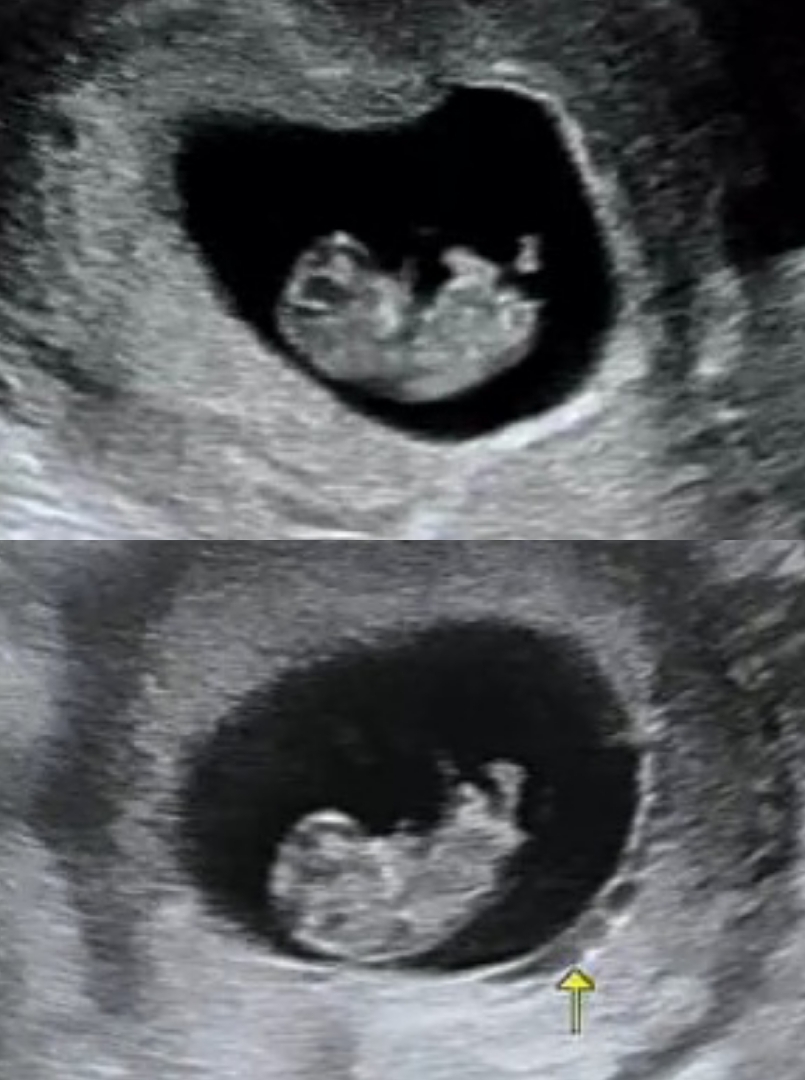

ㅋㅋㅋㅋㅋㅋ같은 배에서 생긴 아가들이라 자라는 포즈도 비슷한가봐요 넘귀엽ㅠㅠ

위에는 첫째 9주4일째, 밑에는 둘째 9주0일째 모습이에요 ㅋㅋㅋ 우리애들은 정면 모습 안보여줘서 젤리곰 사진은 둘다 획득 실패네요🥺 간혹 보면 정면 하리보들 있던데~ 부러워서 일부러 둘째는 조금 일찍 가보았는데 다리는 나오고 불완전한 2등신이네요 ㅋㅋㅋ 그러거나 말거나 건강히 잘 있어서 넘 다행이에요🥹 요며칠 공복입덧도 없어지고 입맛은 뚝 떨어진 채 그어떤 증상도 느낄 수 없어서 어젯밤 잠도 못자고 걱정했거든요😟

발모양 왜케 기욥나용ㅋㅋㅋㅋㅋ뻥뻥 차는것같은 다리모양ㅋㅋㅋㅋㅋㅋ

팔다리 훠이훠이 웃겨요 ㅋㅋㅋ 2센치 조금 넘는 몸에 달린 팔다리🤭